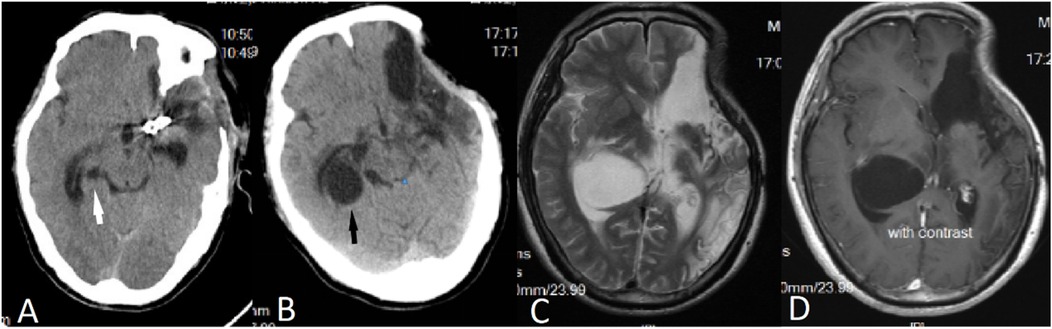

A 50-year-old male patient was admitted with a complaint of a persistent headache lasting for three hours. His medical history was notable for a 20-year history of smoking, with no evidence of hypertension or diabetes. Upon physical examination, the patient was found to be alert and oriented, with a Glasgow Coma Scale (GCS) score of 15 (E4V5M6). The pupils were bilaterally isocoric at 3.0 mm and exhibited intact light reflexes. Signs of meningeal irritation were absent, and no significant neurological deficits were detected. Cranial computed tomography (CT) and computed tomography angiography (CTA) revealed a subarachnoid hemorrhage and an aneurysm of the left internal carotid artery at the ophthalmic segment (Figures 1A,B). He was classified as Hunt-Hess grade II and modified Fisher grade III. The patient underwent a craniotomy for aneurysm clipping. The initial postoperative CT scan of the head demonstrated post-clipping alterations and a marked reduction in the intracranial hematoma relative to prior imaging (Figure 1C). Following this, the patient was administered continuous lumbar drainage of hemorrhagic cerebrospinal fluid (CSF) in conjunction with appropriate supportive care. Three weeks postoperatively, the patient demonstrated a favorable recovery and was discharged without complications. However, 10 days after discharge, the patient was readmitted in a state of sudden coma. The left pupil was noted to be dilated with an absent light reflex. An emergency cranial CT scan revealed the formation of a hematoma in the left frontotemporal lobe, indicating the possibility of rebleeding at the surgical site (Figure 1D), the patient underwent an emergency craniotomy for the evacuation of a hematoma. Intraoperative exploration revealed a recurrent and reruptured aneurysm located in the ophthalmic segment. Successful aneurysm clipping was achieved, along with hematoma evacuation and decompressive craniectomy (Figure 1E). The procedure was completed without complications. After an uncomplicated clinical recovery, the patient was discharged. The pre-discharge follow-up cranial CT scan showed postoperative changes in the brain, with no other significant abnormal findings observed (Figure 1F). Fifteen days post-discharge, the patient exhibited cognitive decline and left-sided weakness. A readmission cranial CT scan revealed a cystic lesion located dorsal to the right ambiens cistern and medial to the parahippocampal gyrus (Figure 2A). Serial imaging conducted at a three-month interval demonstrated progressive enlargement of the cystic lesion (Figure 2B). Subsequent cranial magnetic resonance imaging (MRI) excluded the presence of gliomas and cholesteatomas (Figures 2C,D). One year later, amidst ongoing neurological deterioration, follow-up cranial CT indicated further expansion of the cystic lesion, accompanied by a significant mass effect (Figures 3A,B). Neuroendoscopic exploration was conducted under general anesthesia, during which a cortical fenestration of the temporal lobe was created to facilitate access to the cystic cavity. Intraoperative observations revealed a thickened cyst wall under high tension with evidence of vascular proliferation. The cystic fluid was colorless and transparent, lacking hemosiderin deposition (Figures 4A–C). An arachnoid cyst was suspected intraoperatively, prompting partial resection of the cyst wall and the creation of a lateral ventriculostomy. The fistulous opening measured approximately 2.5 cm in diameter, facilitating communication with the lateral ventricle (Figure 4C). Histopathological analysis of the cyst wall confirmed the diagnosis of an arachnoid cyst (Figure 5). Following the surgical procedure, the patient demonstrated a gradual enhancement in left-sided motor weakness and cognitive abilities. At the three-month follow-up, both motor and cognitive functions had nearly returned to baseline levels. The GCS score was recorded at 15 (E4V5M6). The latest cranial MRI revealed a substantial reduction in cyst volume, accompanied by a complete resolution of the mass effect (Figures 3C,D).

Figure 2. (A) Fifteen days post-surgery, a CT scan revealed the presence of an arachnoid cyst located dorsal to the right ambient cistern and medial to the parahippocampal gyrus (indicated by a white arrow). (B) A follow-up CT scan conducted three months later demonstrated an enlargement of the arachnoid cyst (indicated by a black arrow). (C,D) Subsequent MRI findings indicated that the cystic fluid exhibited a signal identical to that of CSF, with no enhancement observed on the contrast-enhanced scan.